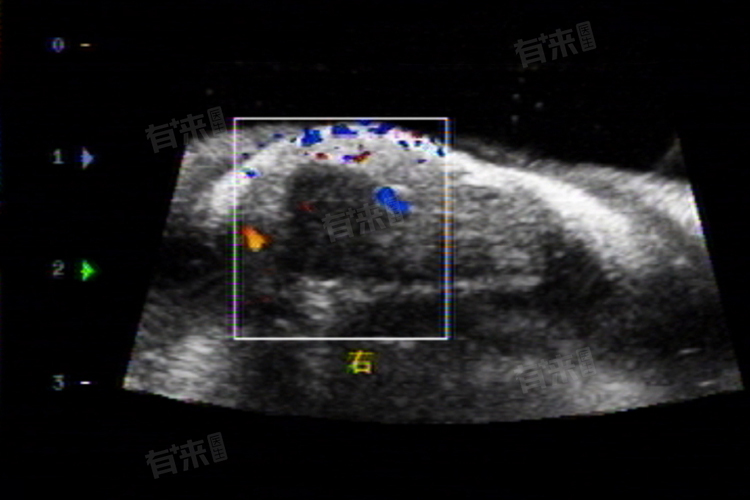

1、疾病诊断:超声诊断科通过对不同器官和组织的超声检查,如心脏、腹部、妇产科、浅表器官,如甲状腺、乳腺等及血管等,帮助医生诊断各种疾病,如心脏病、肝病、肾病、肿瘤、血管病变等。

3、引导与治疗:超声诊断科还负责在超声引导下进行各种治疗操作,如穿刺活检、囊肿抽液、置管引流等,以及在超声引导下的介入治疗,如肿瘤消融、血栓溶解等,为患者提供更加精准、安全的治疗方案。